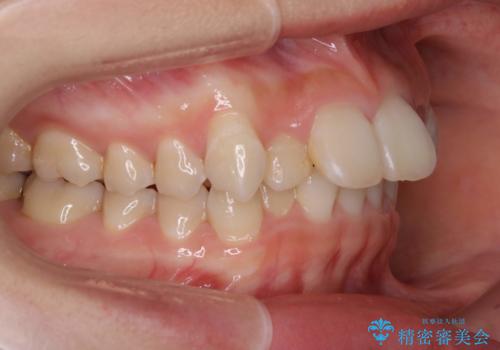

ハーフリンガル矯正 抜歯をして前歯を下げる

- 上顎の両側第1小臼歯抜歯による抜歯矯正を計画した。

上顎の抜歯により上の前歯の位置を大幅に後ろに下げることができます。

奥歯の位置関係など、様々な要素を加味し、適応を判断する必要があります。